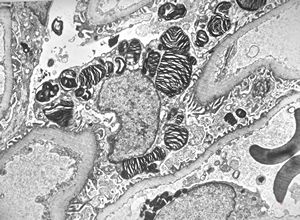

F,69y. | urinary bladder - malakoplakia